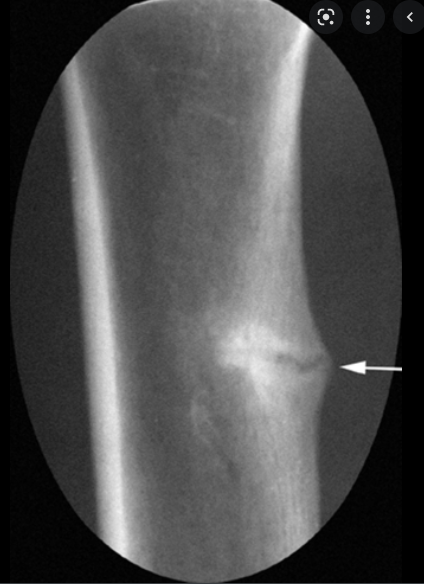

What would you see on an X-ray of someone with osteomalacia?

looser zones

What are looser zones?

spontaneous incomplete fractures